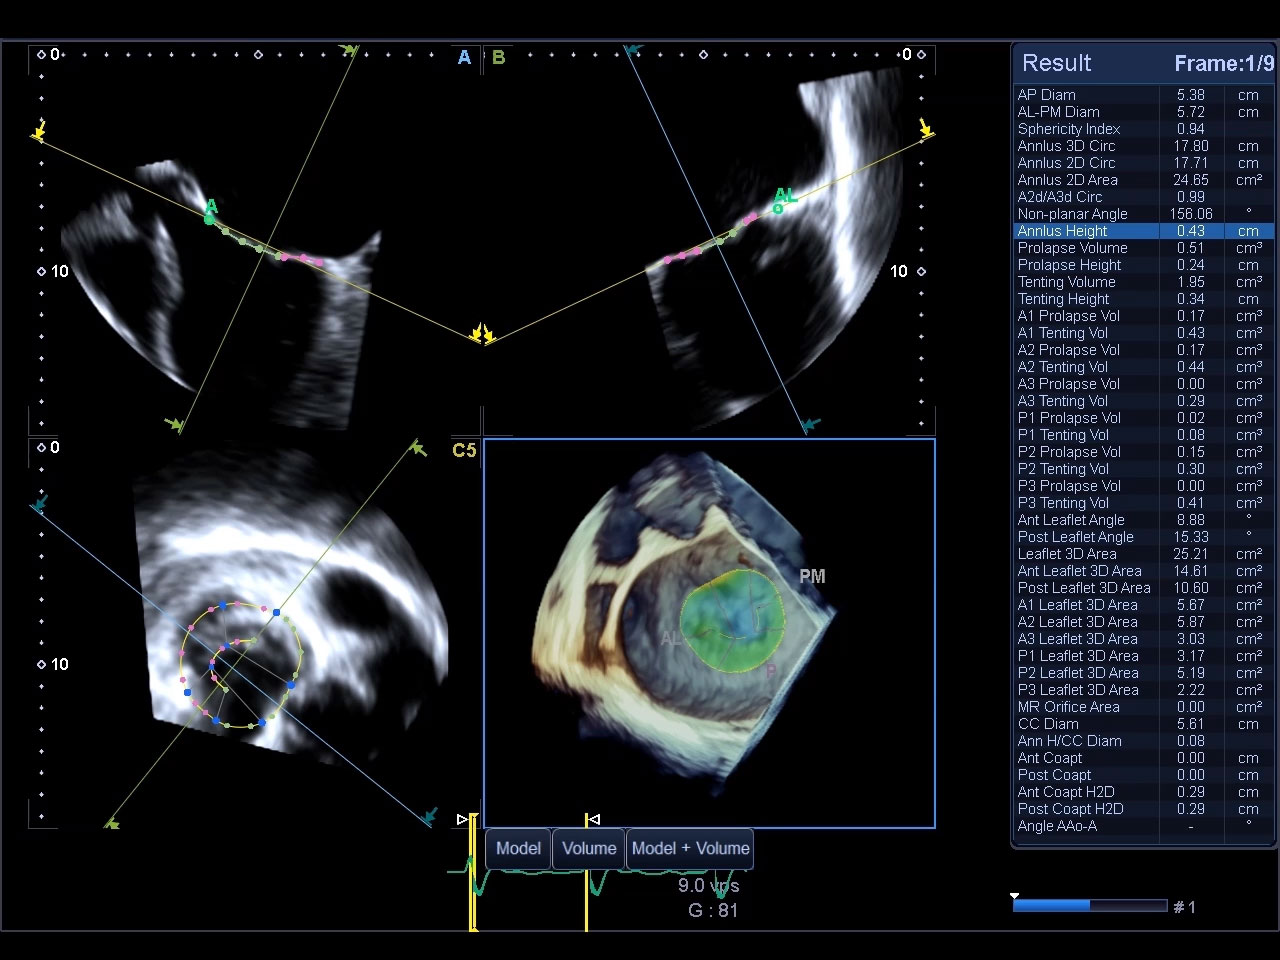

Anatomic and functional assessment

of the mitral valve.

4D Mitral Valve Analysis*

The 4D MVA tool provides concise anatomic and functional assessment of the mitral valve. The function’s quad display offers a clear overview of different scan planes.

- Functional assessment of the Mitral Valve

- Intuitive color-coded 3D function analysis

- Quad display (different scan planes, 3D)

Watch Mitral Valve Analysis Demo

*Available on the Aplio i900 only.